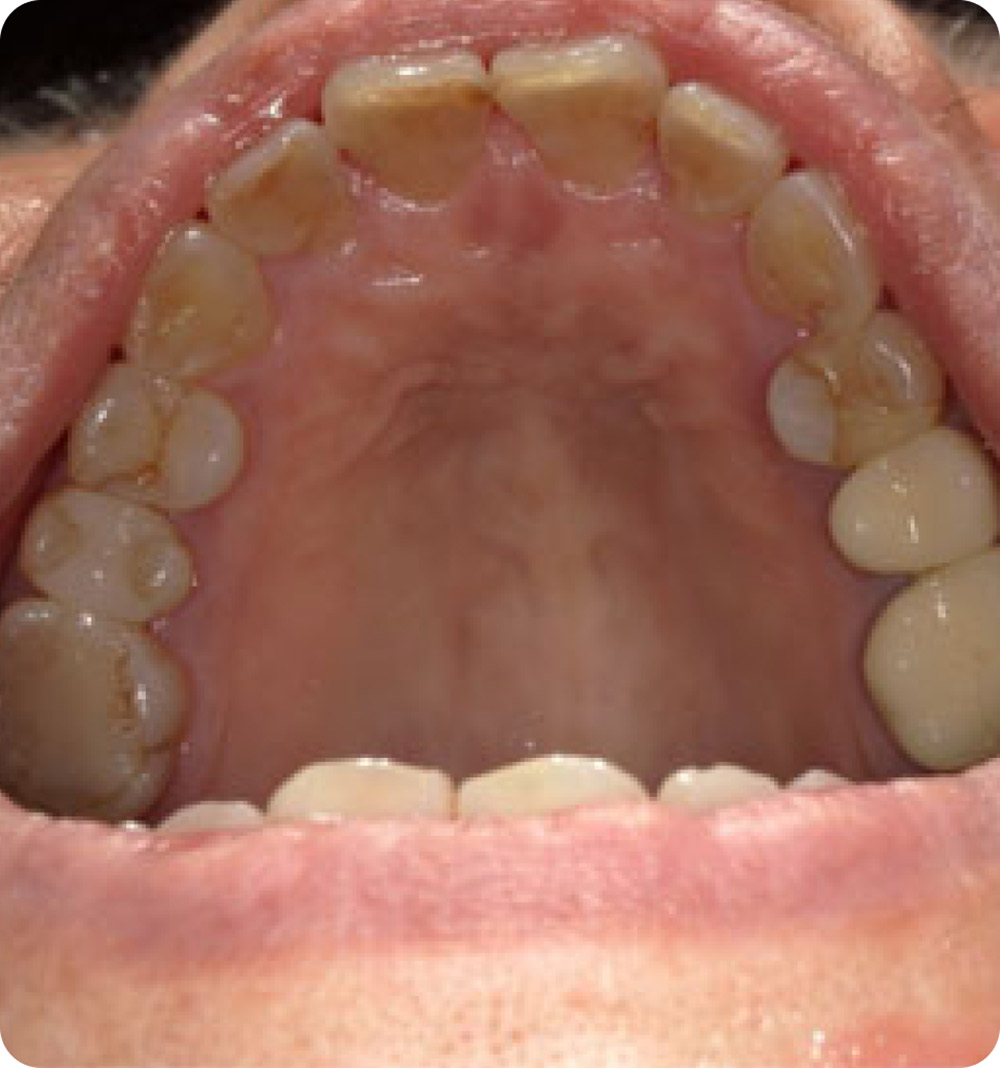

マウスピース矯正症例 術後

術後

年齢 70代(女性)

主訴 上の歯ならびがガタガタなのが気になる

期間・費用 上顎のみ8か月 264,000円(税込)

リスク

• 処置後一時的にしみや痛みがでることがある。

• 生活習慣によっては矯正後の後戻りの可能性がある。